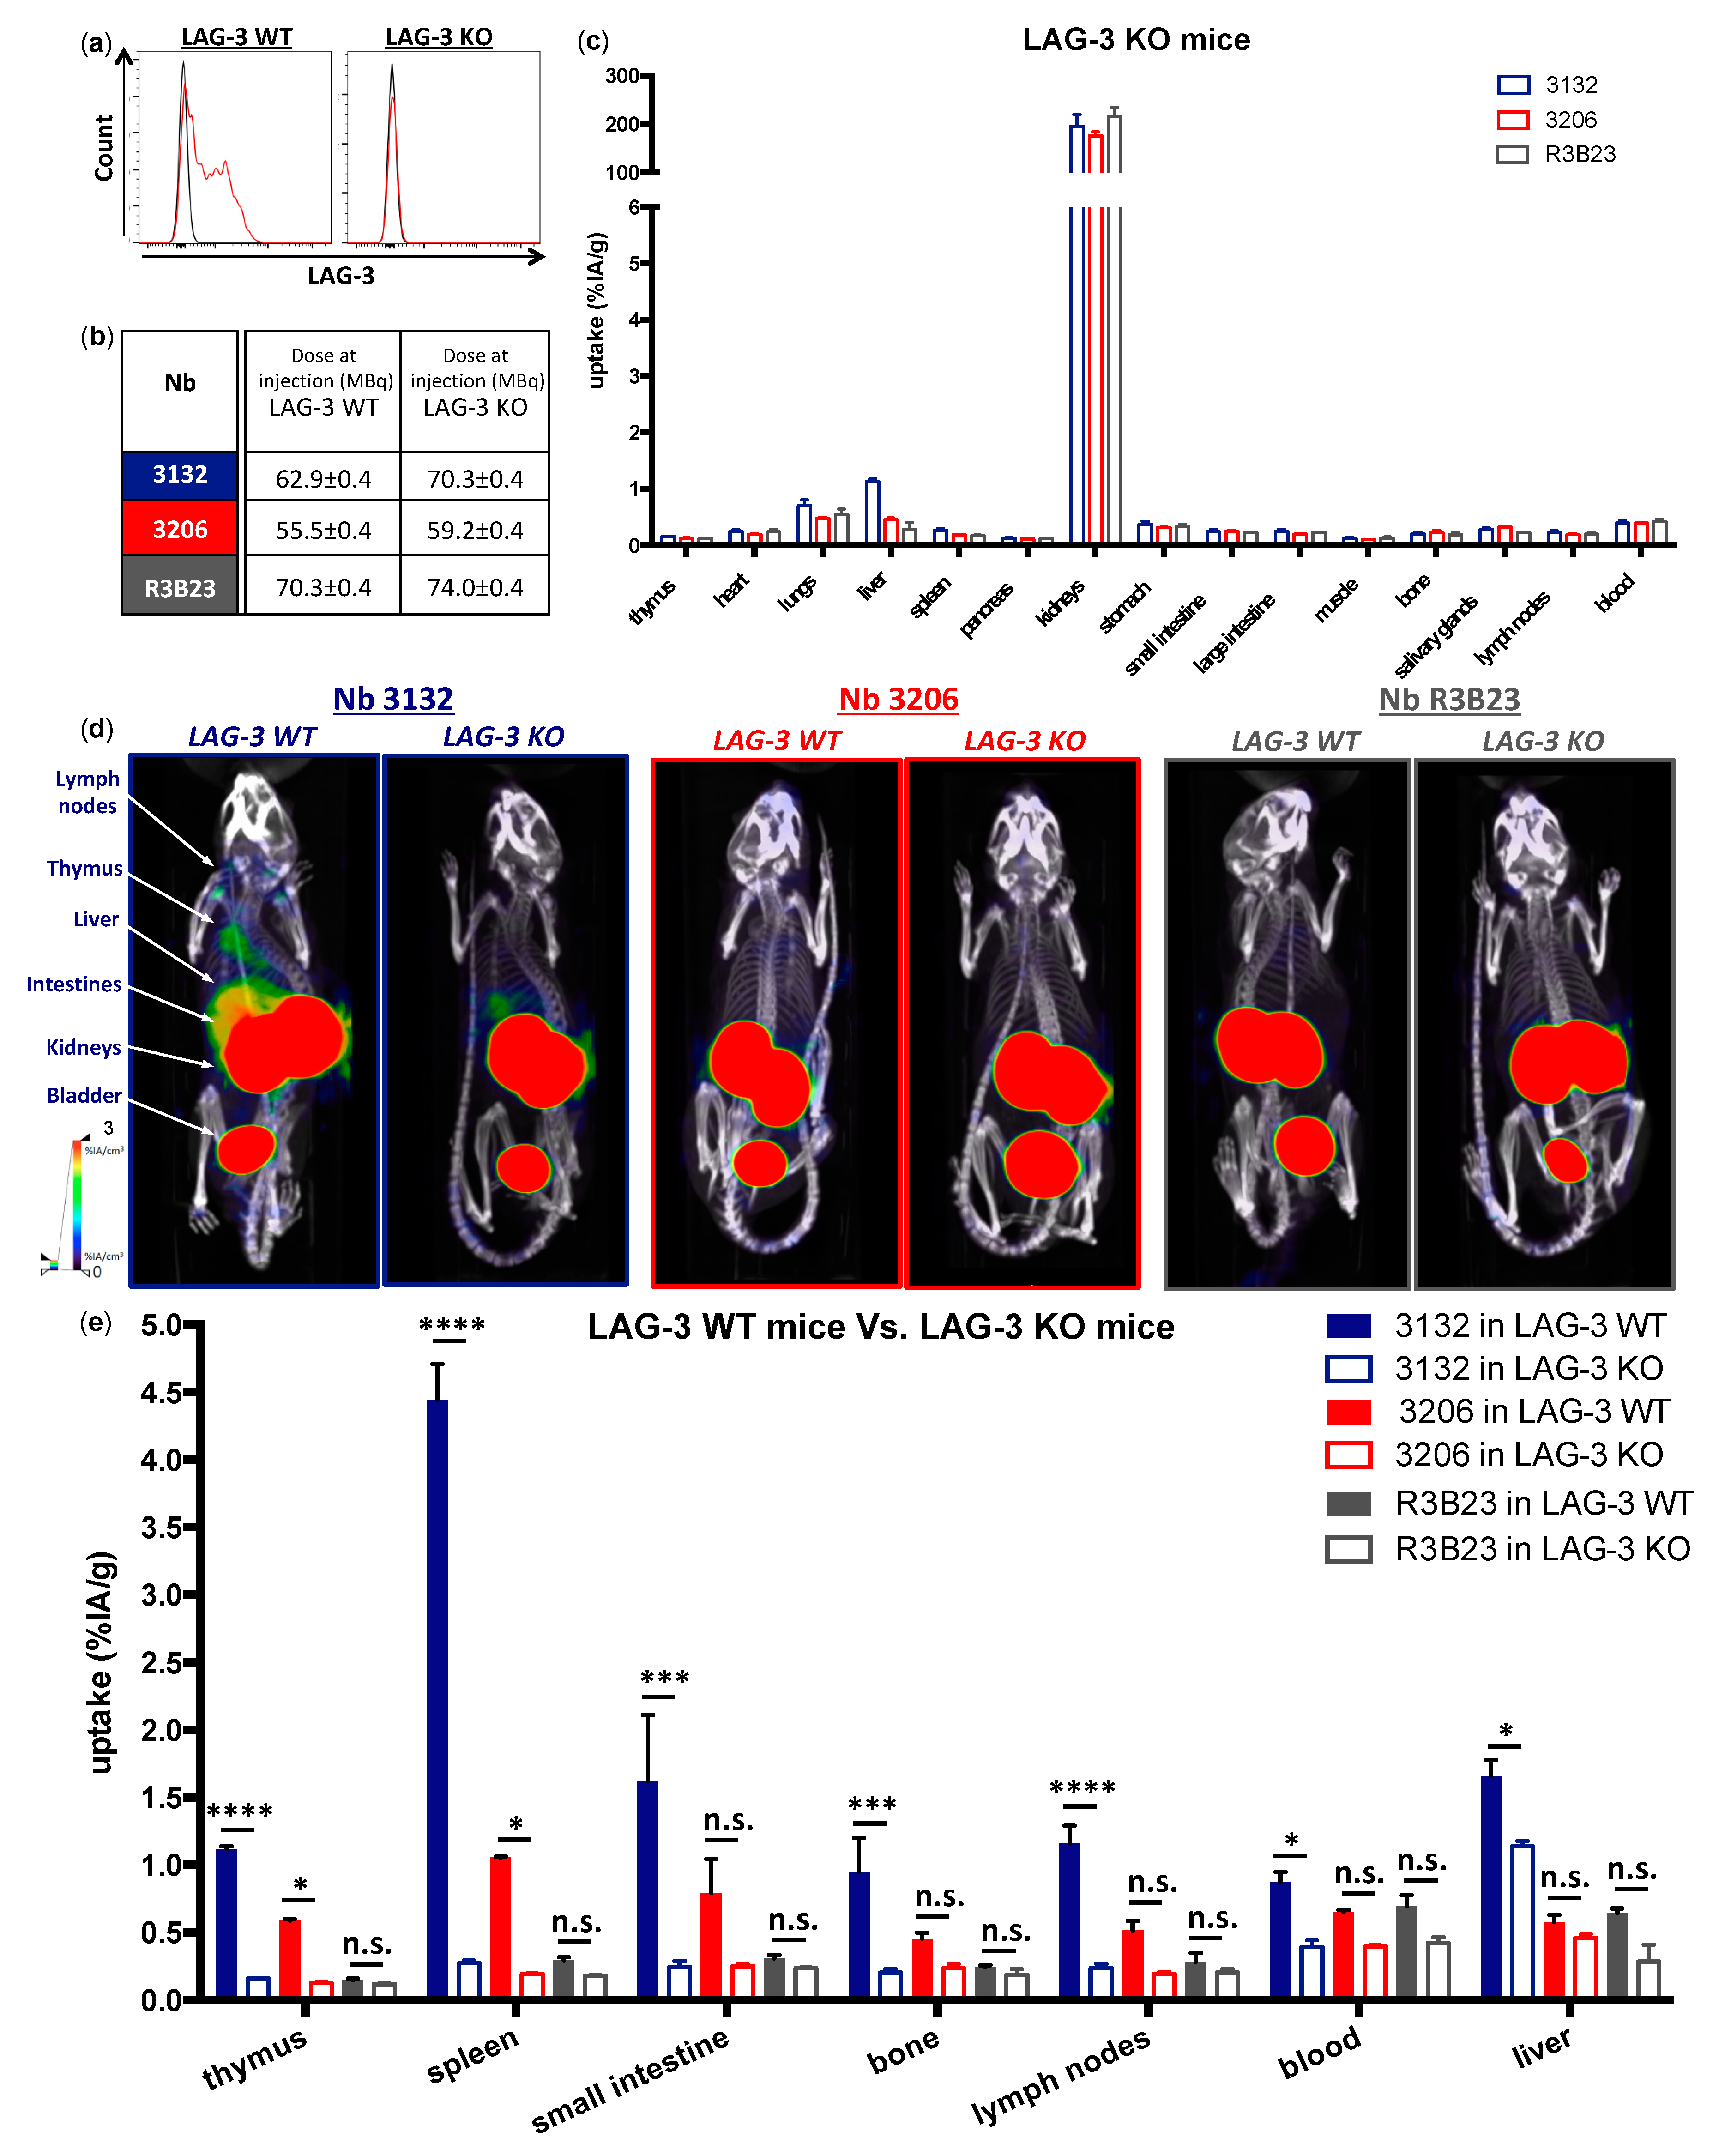

We showed that lymphocytes, residing in the lymph nodes of naive and healthy C57BL/6 mice, express low levels of moLAG-3. In contrast, lymph node residing antigen presenting cells expressed higher levels of moLAG-3. Within the spleen, the immune cell population (CD45

+) with the highest moLAG-3 expression could be detected on antigen-presenting cells, like dendritic cells and macrophages, and on NK and NKT cells [

4]. Moreover, very low amounts of moLAG-3 are expressed on CD19

+ B cells, and CD4

+ and CD8

+ T cells, which is comparable to the low levels found on lymphocytes isolated from lymph nodes. Nevertheless, out of nine different

99mTc-labeled anti-moLAG-3 Nbs, Nb 3132 was still able to detect and visualize low levels of moLAG-3 expressing immune cells residing in the spleen and lymph nodes. Although the affinity of Nb 3132 for moLAG-3 is rather low, injection of

99mTc-labeled Nb 3206, with a 10-fold higher affinity for moLAG-3, was less able to detect and image moLAG-3 expressing cells in the spleen and lymph nodes. Interestingly, when evaluating our Nbs for binding on moLAG-3 expressing cells using flow cytometry, Nb 3132 showed the highest binding of all Nbs. This observation could mean that recombinant moLAG-3 coated chips for SPR or membrane expressed LAG-3 for flow cytometry analysis are not completely identical and thus could lead to under or overestimation of Nb affinity. Moreover, the affinity of Nbs is only one of the parameters used to predict its potential for imaging purposes. Vaneycken et al. showed that the dissociation rate of Nbs did not correlate with tumor uptake since their Nb with the slowest dissociation rate targeted poorly to tumors, while another Nb, with a fast dissociation rate, targeted very well [

40]. Nevertheless, the specific uptake for

99mTc-labeled anti-moLAG-3 Nb 3132 and 3206 was further validated using LAG-3 KO mice, where no uptake could be detected in organs like spleen and lymph nodes, expect for the liver. However, the uptake of

99mTc-labeled Nb 3132 in the liver of LAG-3 KO was significantly lower compared than in LAG-3 WT mice, suggesting that accumulation was partly due to specific binding. To this date, no supportive data could be found in literature describing LAG-3 expression in the liver. Several studies have reported non-specific uptake of radiolabeled Nbs in the liver, explaining the remaining liver uptake in LAG-3 KO mice [

39]. Unfortunately, the nonspecific accumulation in the liver could obscure possible liver metastases and such accumulation should be taken into account when selecting Nbs for the noninvasive imaging of human LAG-3 since these are most likely to reach the clinic compared to moLAG-3 targeting Nbs.